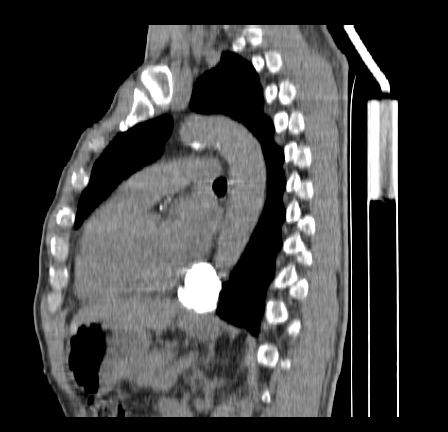

以下是引用影像孺子牛在2009-5-20 23:18:00的发言:[br]左侧后心膈角处类椭圆形钙化灶,最常见的是淋巴结钙化,但太大了不支持,其它如食管囊肿钙化、实性畸胆瘤等。何东西钙化真不好定。

以下是引用zbp537在2009-5-20 20:52:00的发言:[br]钙化灶,来源不好说。